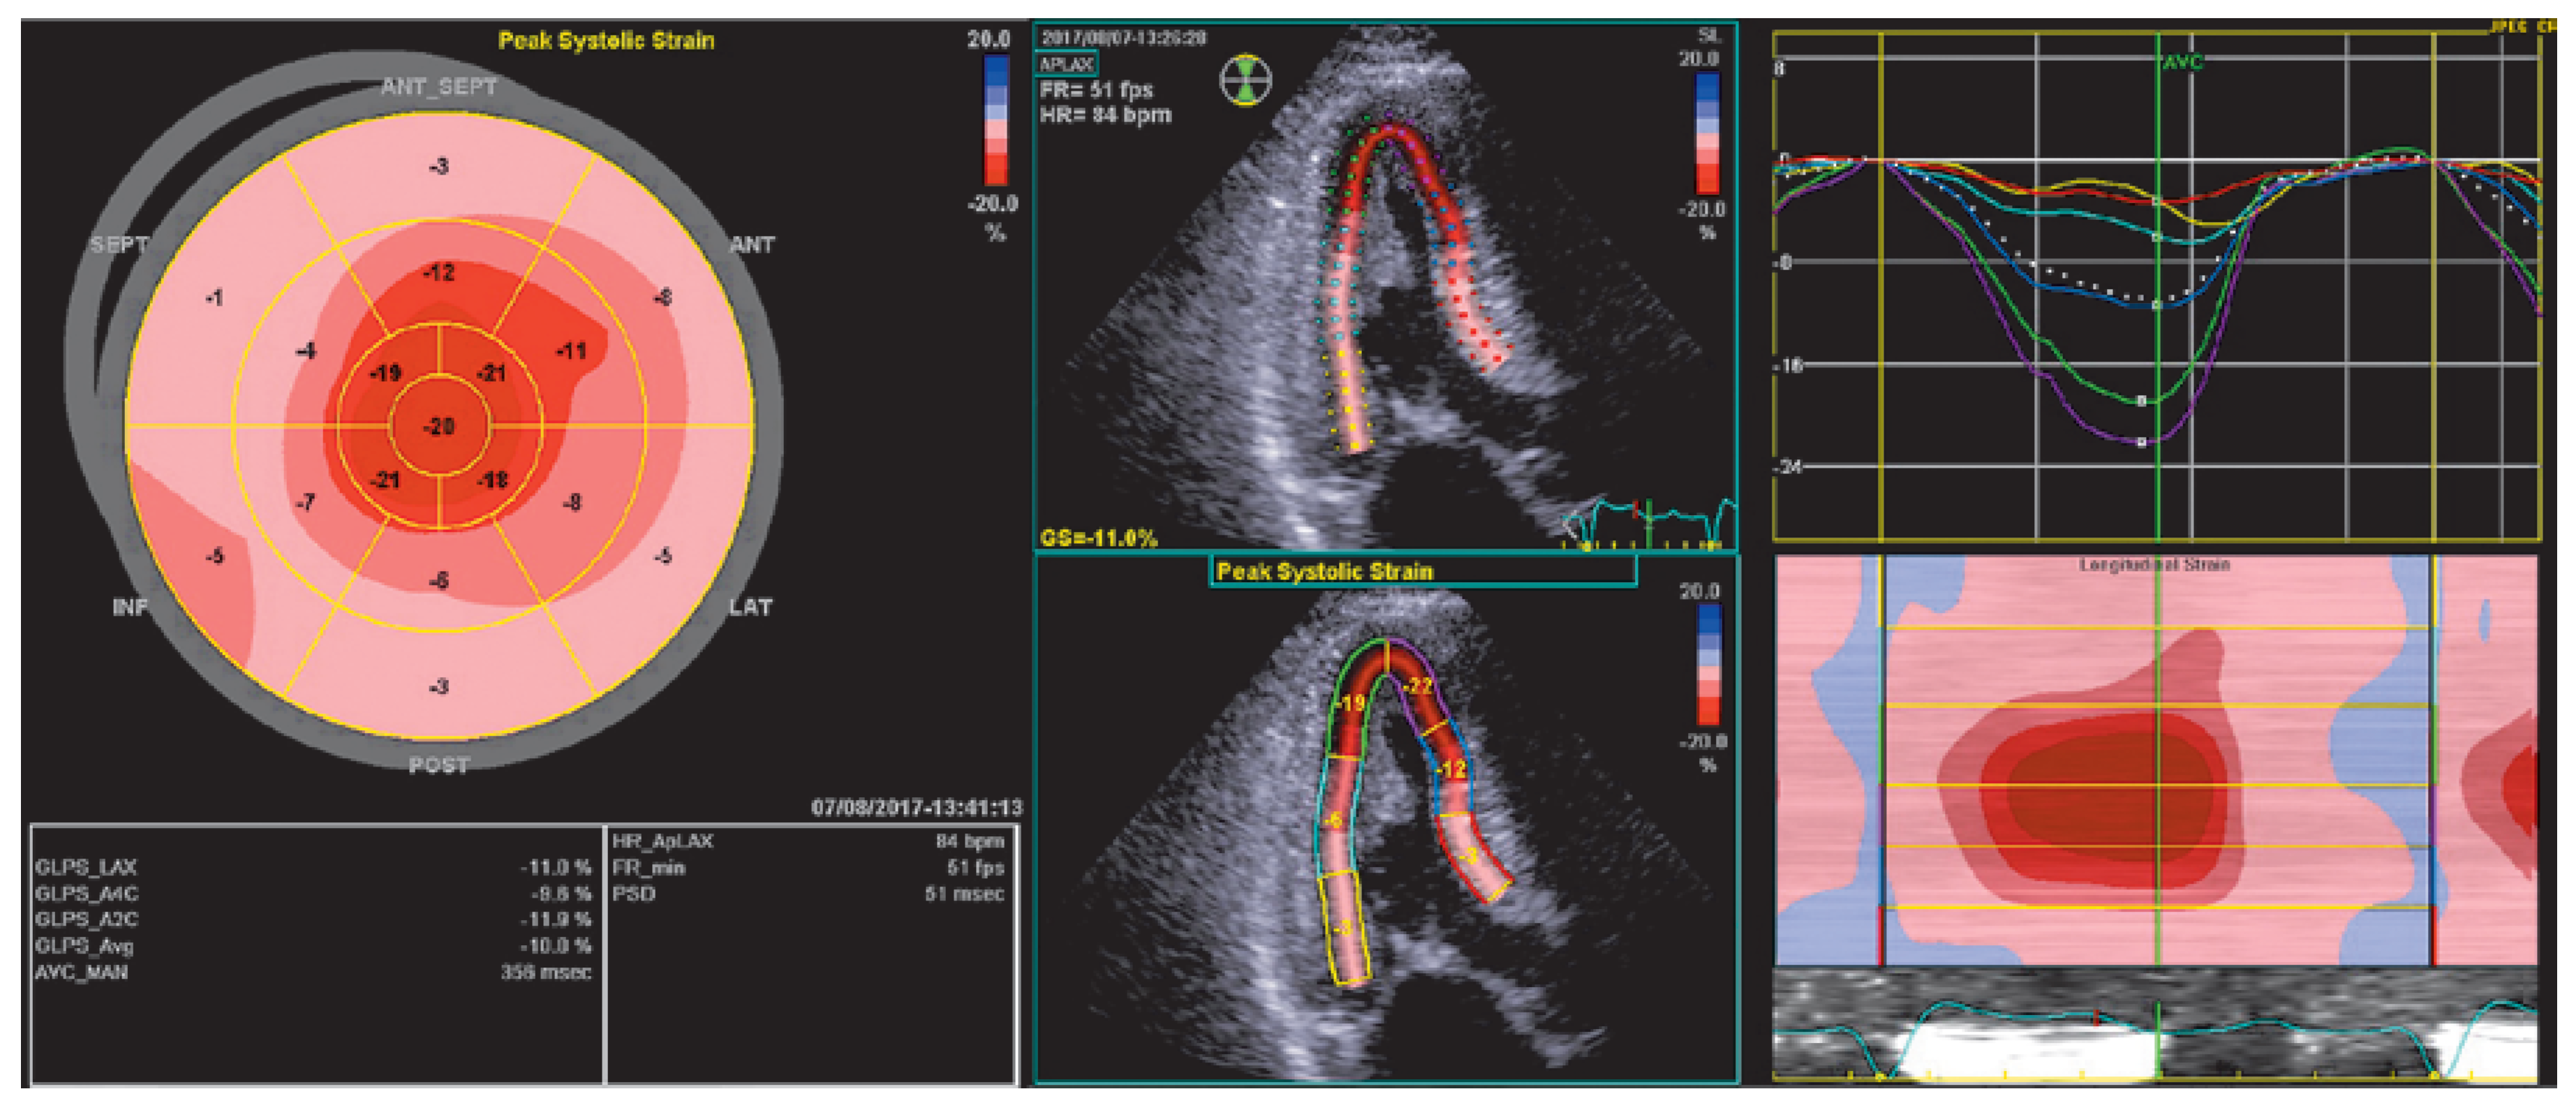

How do we diagnose cardiac amyloidosis?